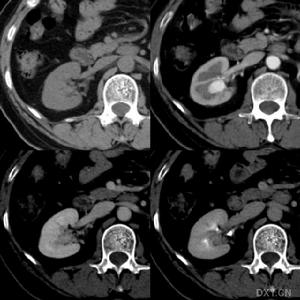

(4)電子計算機X線體層掃描(CT):能較準確的檢測腎皮質瘢痕。

慢性反流性腎病(1)尿路造影:本病最典型的改變是與扭曲的腎盞對應的皮質局灶性瘢痕。殘餘小葉可代償性肥大,呈現假性腫瘤影像,一般而言,患者尿路造影表現典型,呈現為“標準”影像。腎臟瘢痕對應扭曲且杵狀膨大的腎盞正常皮質與之交替,在假性輸尿管腎盂連線部梗阻時腎臟輪廓可能無特殊。當病變部位嚴重萎縮覆蓋杵狀腎盞的皮質變薄其他部位代償性肥大時腎輪廓也可無特殊

(2)超音波:超音波檢查顯示腎外形不規則,纖維瘢痕部位表現為反射增強代償性肥大部位反射正常。94%的病例超聲與排泄性尿路造影檢查結果具有一致性。超聲檢查探測腎乳頭形態的靈敏性不如靜脈內腎盂造影但能靈敏探測腎臟瘢痕靜脈內腎盂造影對此效果差

(5)電子計算機X線體層掃描(CT):對檢測腎皮質瘢痕較準確惟價格較昂貴。